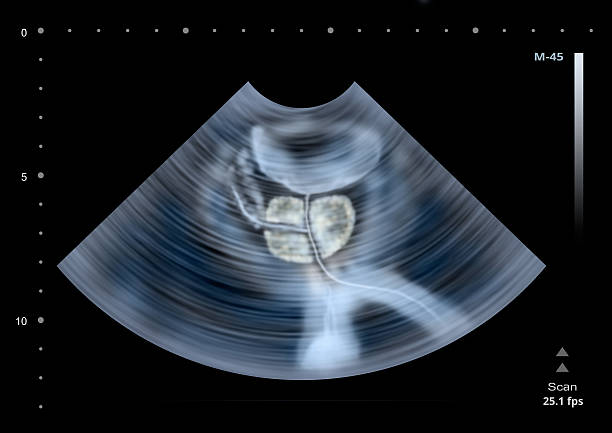

먼저 전립선염을 진단하기 위해 환자의 과거력과 증상을 검사합니다. 먼저 직장촉진, 일반소변검사, 전립선마사지 후 전립선액검사 등을 통해 원인을 찾는다. 원인이 밝혀지면 증상에 따라 약물, 식이조절, 생활습관 개선 등 손쉬운 방법으로 치료할 수 있습니다. 하지만 평소에 건강관리를 하는 것이 가장 좋으므로 담배, 술과 커피 등을 줄이며 가능한 너무 앉아 있찌만 말고 스트레칭을 하여 몸의 부담을 덜게 하는 것이 전립선을 보다 건강하게 관리할 수 있는 방법입니다.